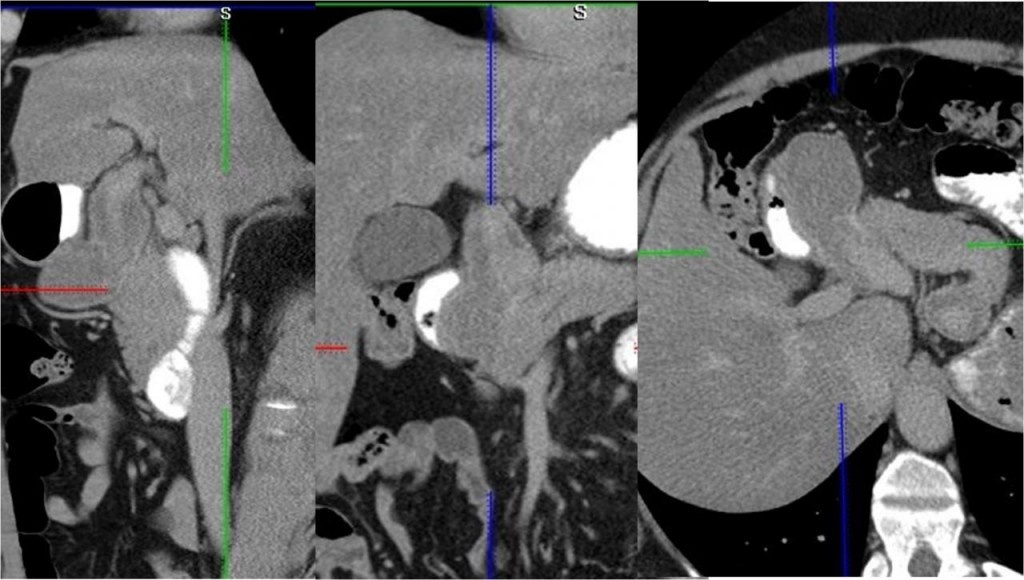

Диагностика при аневризме печеночной артерии

В отсутствие жалоб аневризмы обнаруживают случайно при проведении УЗИ брюшной полости. Проходить плановые обследования для контроля состояния здоровья следует пациентам с сердечно-сосудистыми заболеваниями (в особенности с эндокардитом), болезнями ЖКТ и травмами живота в анамнезе после драк, падений, аварий.

• Назначает УЗИ, дуплексное сканирование сосудов, ангиографию, КТ или МРТ с контрастом.

Аневризмы следует дифференцировать от кист поджелудочной железы, опухолей, язвы желудка, кровотечений при гипертензии. Инструментальная диагностика — основной помощник при постановке диагноза. В лабораторных анализах может не быть никаких изменений.